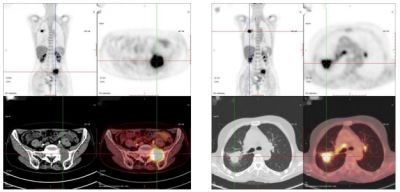

40岁,女,外院查肿瘤标志物示:癌胚抗原(CEA)411.00 ng/ml,糖类抗原19-9(CA19-9)30.0 U/ml;来我科行PET/CT检查。

PET/CT诊断:乙状结肠癌伴肝脏、淋巴结多发转移;随后病理确诊为乙状结肠腺癌。